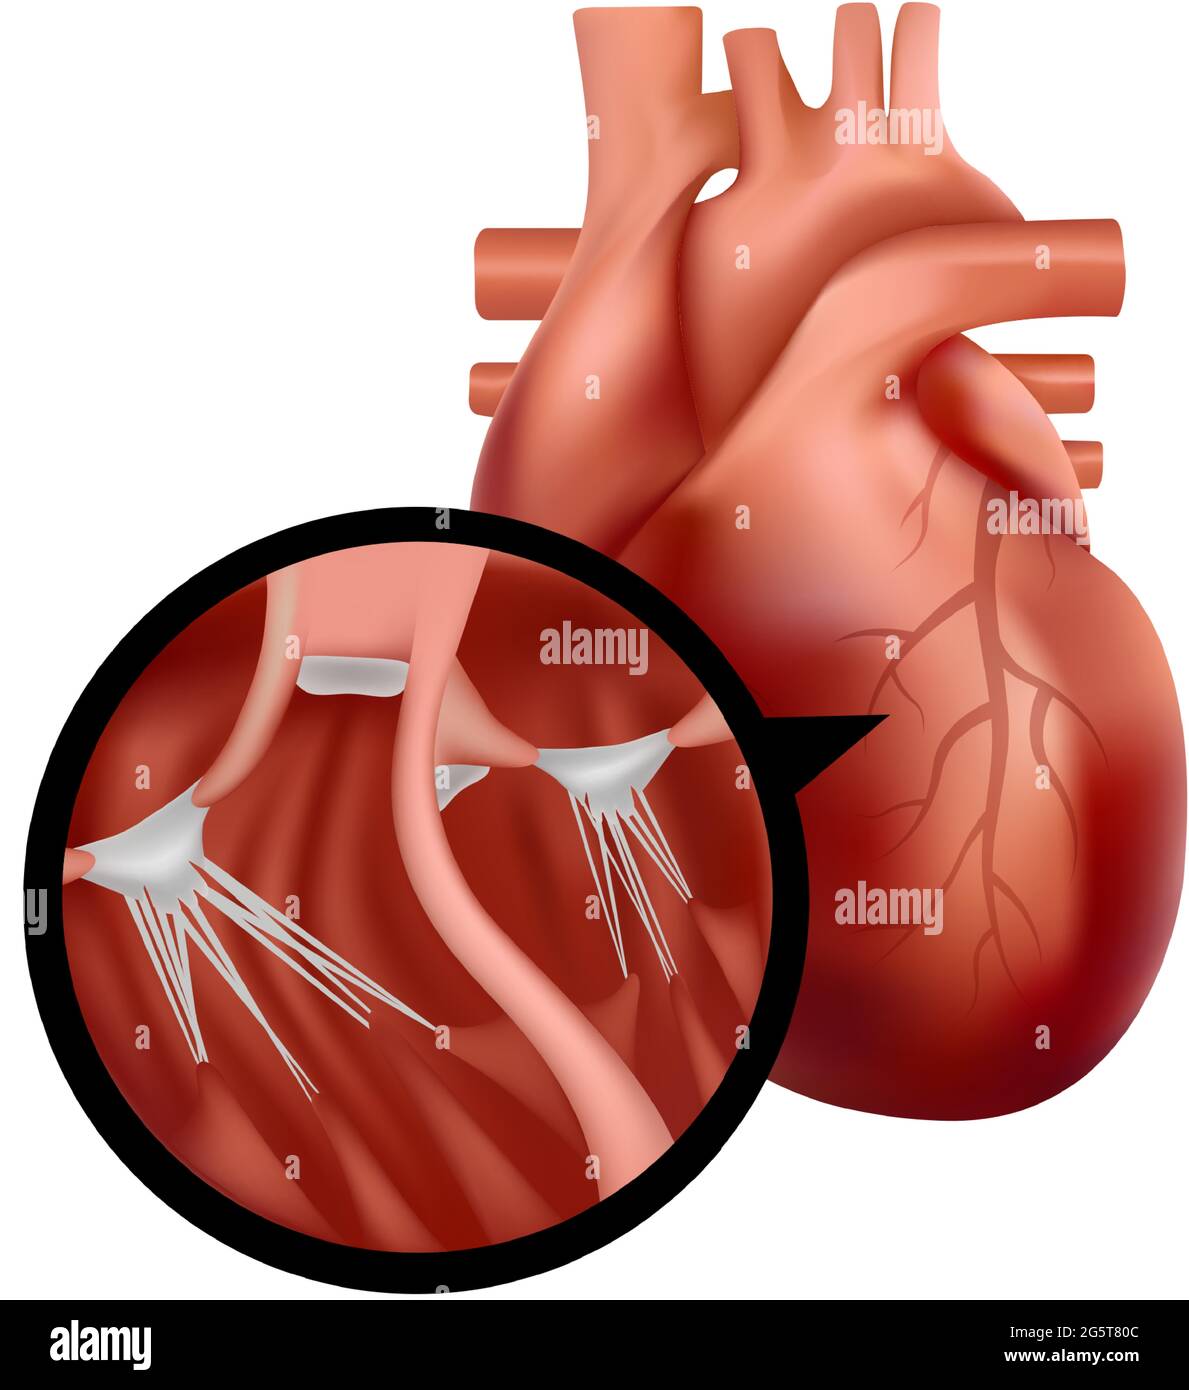

Realistic human heart with cross-section close-up. Heart organ illustration. Stock Vectorhttps://www.alamy.com/image-license-details/?v=1https://www.alamy.com/realistic-human-heart-with-cross-section-close-up-heart-organ-illustration-image433865612.html

Realistic human heart with cross-section close-up. Heart organ illustration. Stock Vectorhttps://www.alamy.com/image-license-details/?v=1https://www.alamy.com/realistic-human-heart-with-cross-section-close-up-heart-organ-illustration-image433865612.htmlRF2G5T80C–Realistic human heart with cross-section close-up. Heart organ illustration.